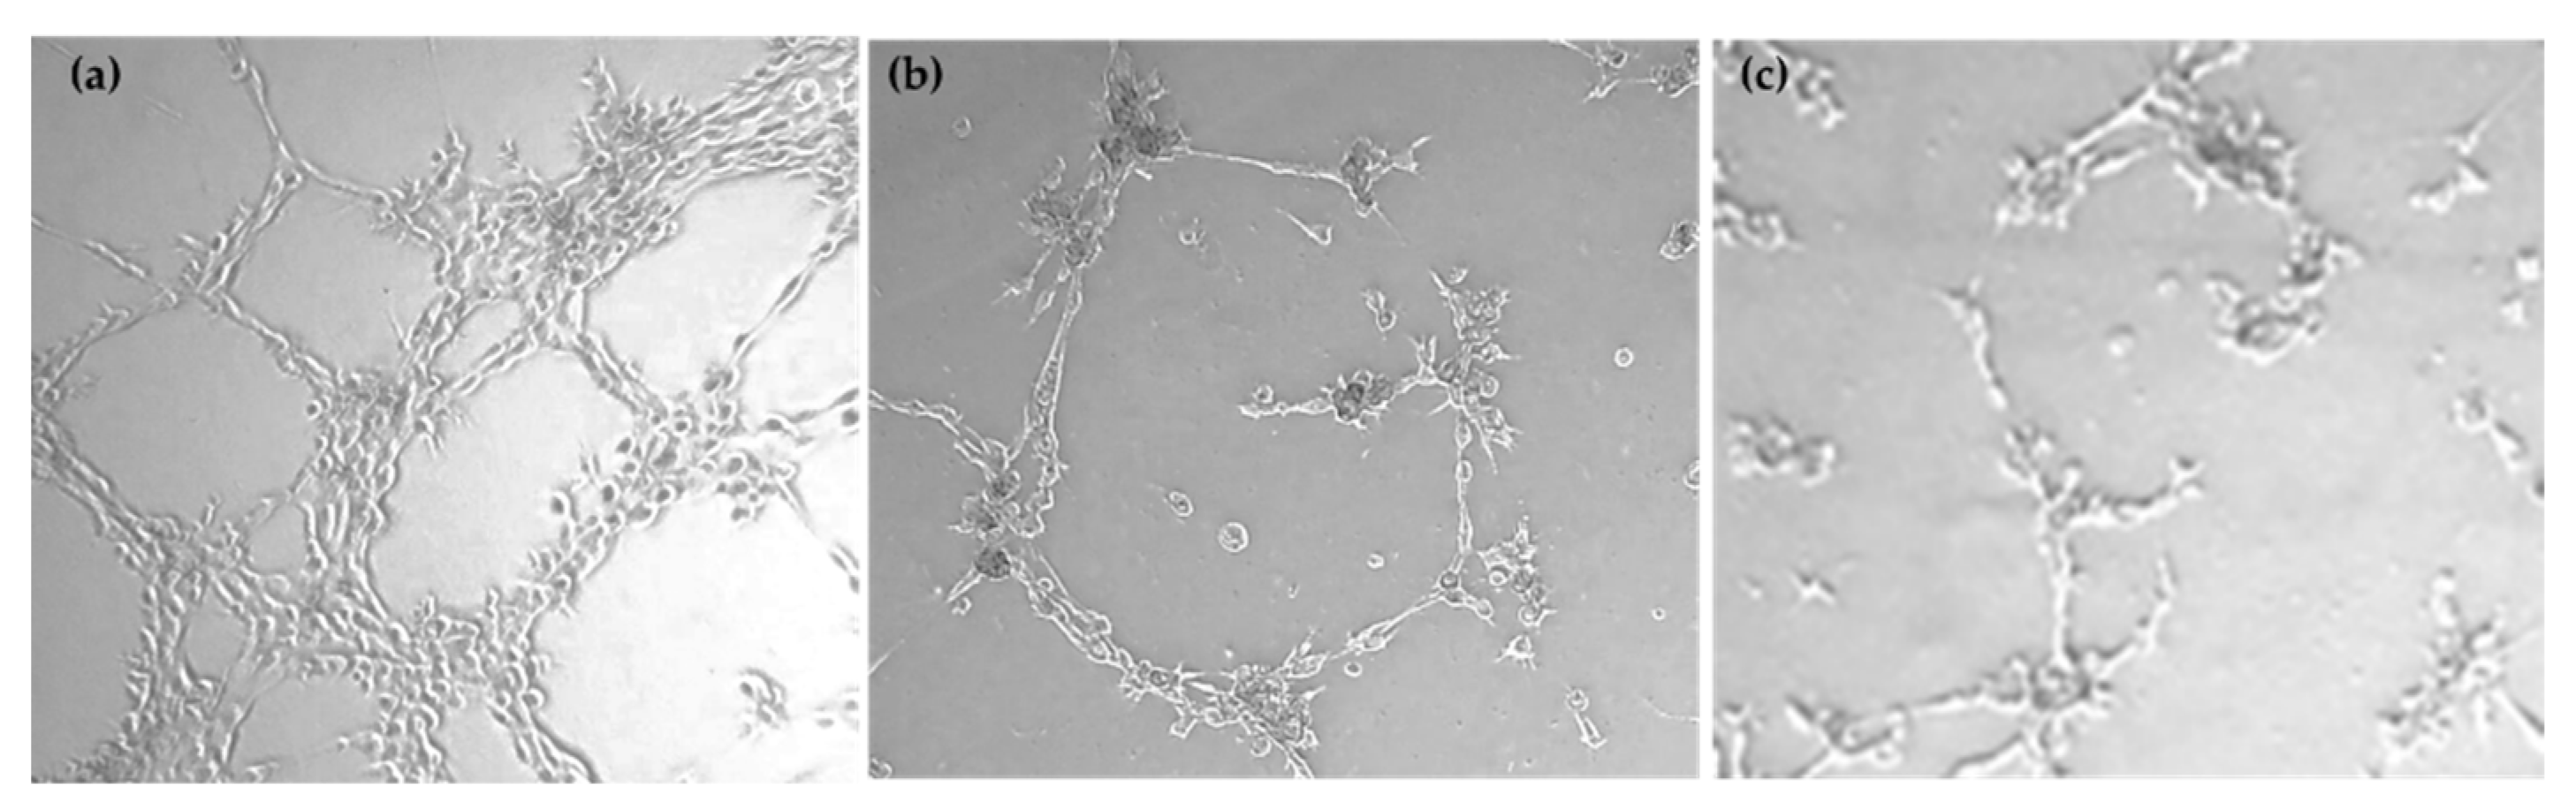

The capacity to inhibit the formation of a new vasculature network formed by HMEC-1 was evaluated on compounds 8 and 14 at different concentrations. Table 5 shows the minimum concentration at which these compounds are active and begin to inhibit the microtube formation.

Pictures for the inhibition of neovascularization achieved by compounds 8 and 14 are displayed in Figure 2.

A comparison of the minimum active concentration values to IC50 values for the HMEC-1 cell line (see Table 1) shows that the compounds exhibited antiangiogenic action while they have no effect on endothelial cell proliferation.

Figure 2. (a) control; (b) 8 at 20 µM (c) 14 at 20 µM (×20 Magnifications).